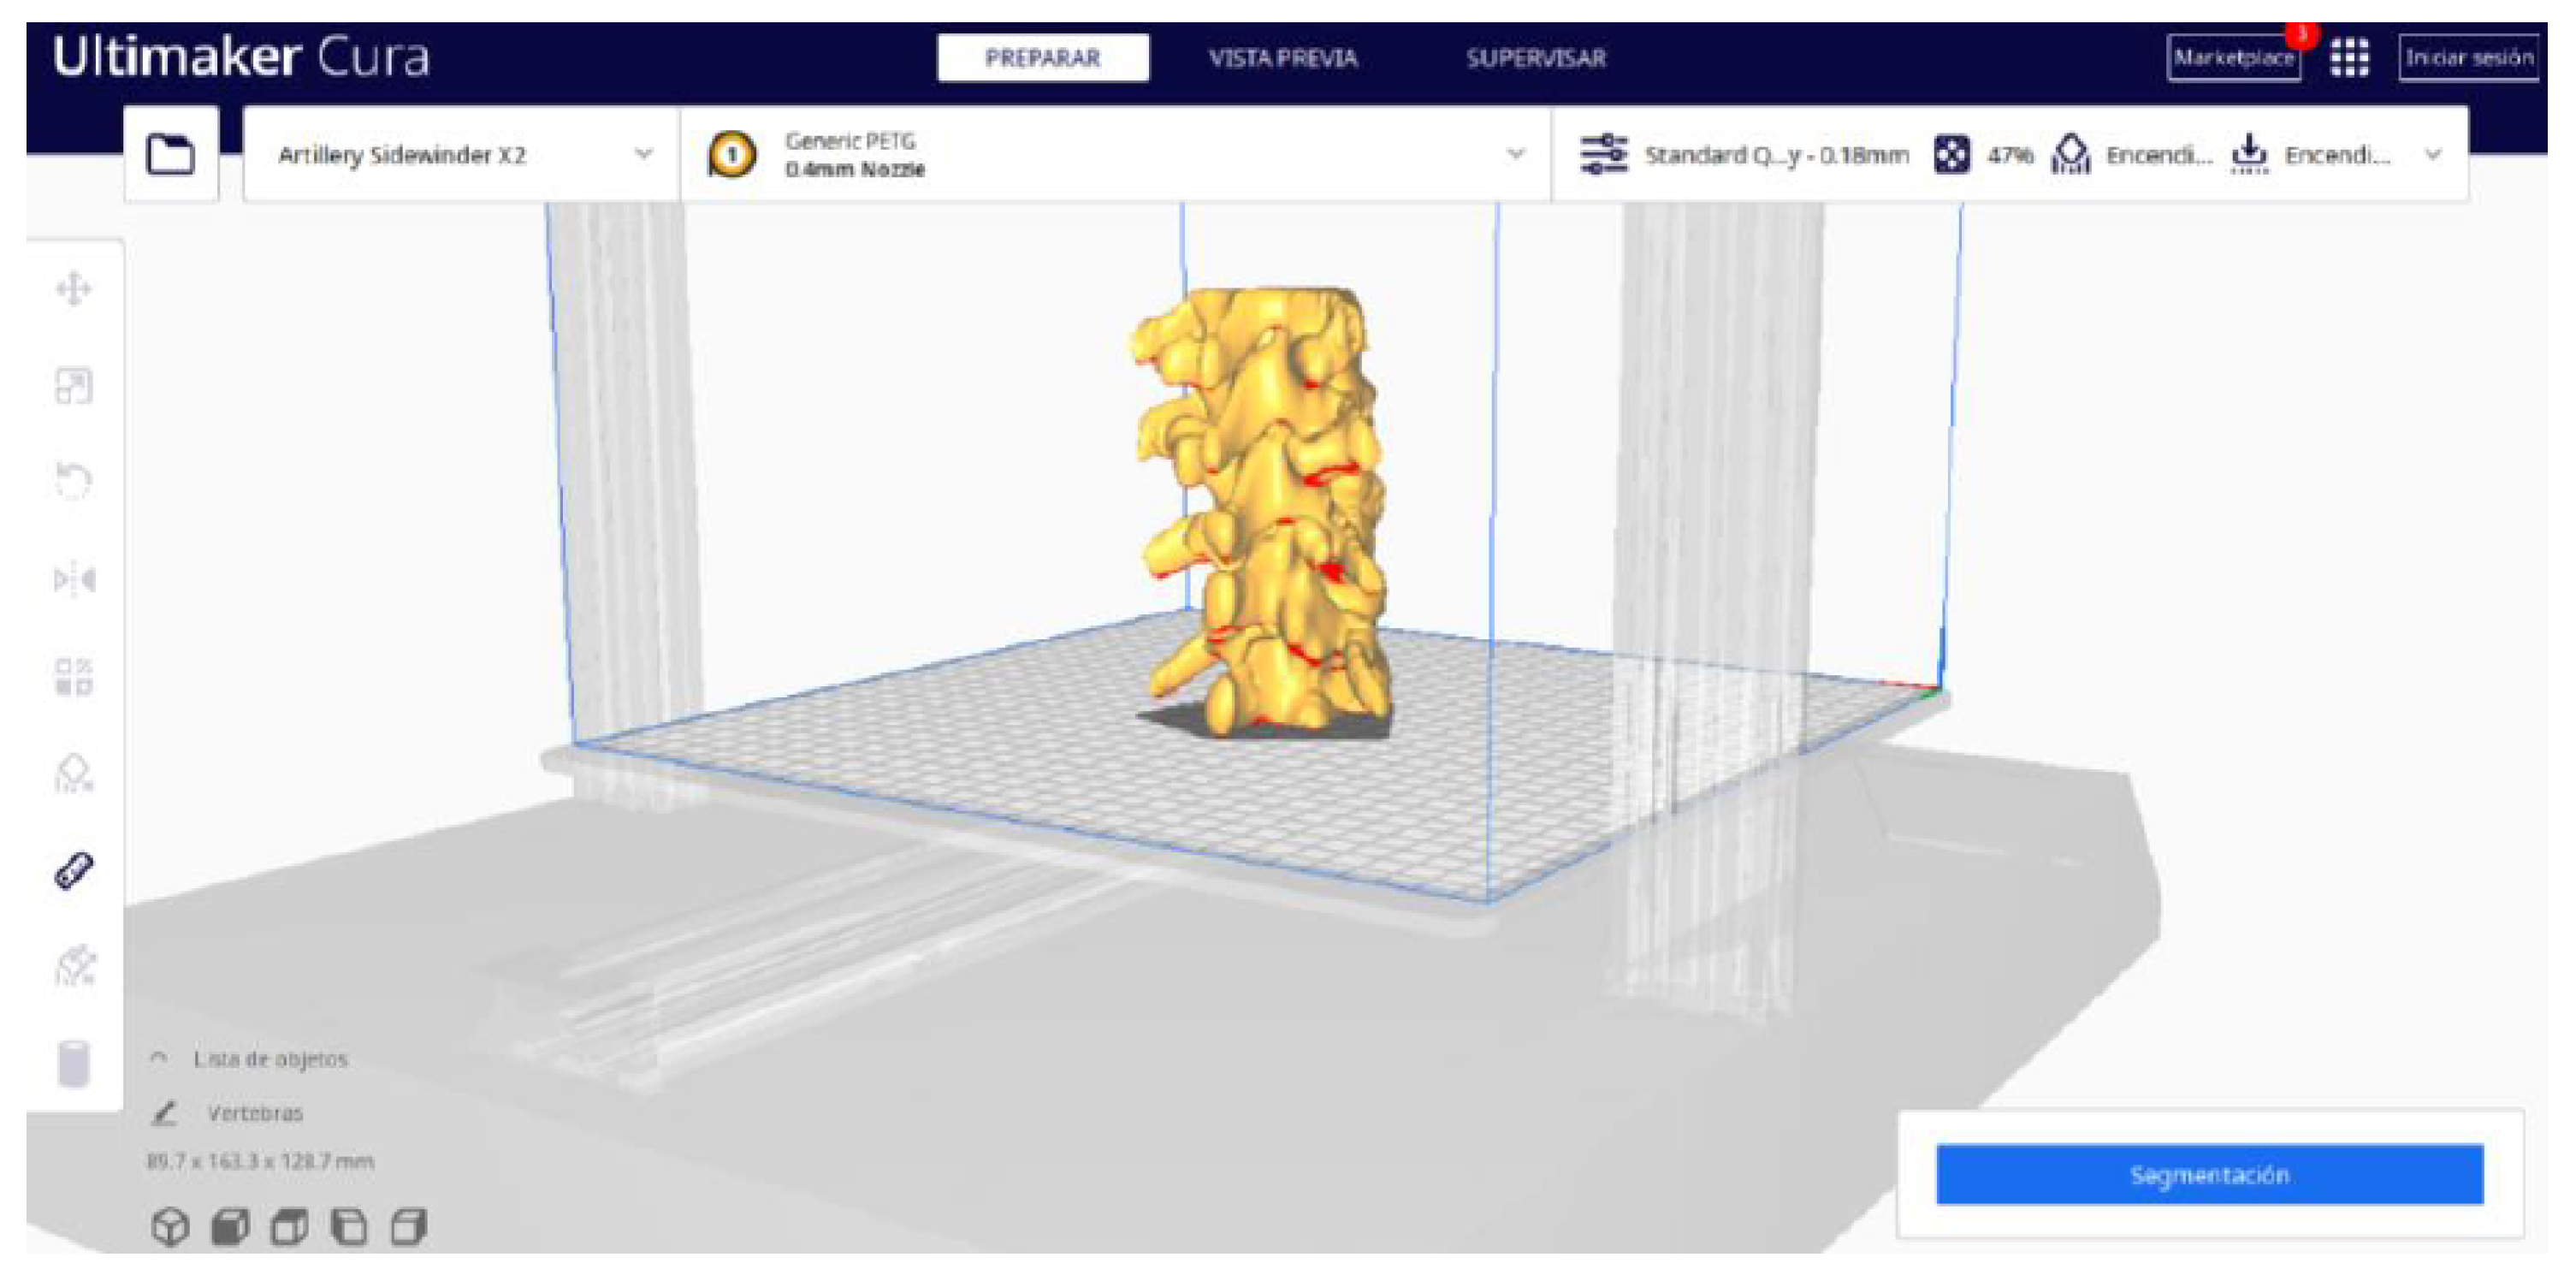

2.2. STL-to-GCODE File Conversion

- Choose the appropriate support structure type and pattern to ensure the successful printing of complex geometries, adjusting the adhesion to the build plate as necessary.

- In order to continue the STL file to GCODE conversion process, select the “Segmentation” option in Ultimaker Cura.

- The segmentation tool provides valuable information such as the estimated model weight and estimated printing time, among other crucial data.

3.1.2. STL-to-GCODE File

| Vertebrae | [150, 300] | Median | 0.8 | 0.18 | 25 |

| Vertebrae models | m; m | Artillery Sidewinder X2 |